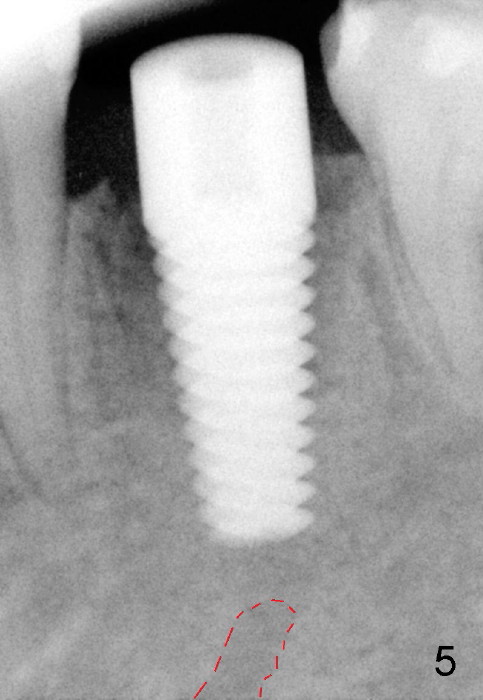

Six months postop, bone density around the implant increases (Fig.9). There is slight gingival recession buccal to the implant (Fig.10 arrow). A short abutment is placed and prepared short (Fig.11 A); the margin is prepared as low as possible in the implant (I).